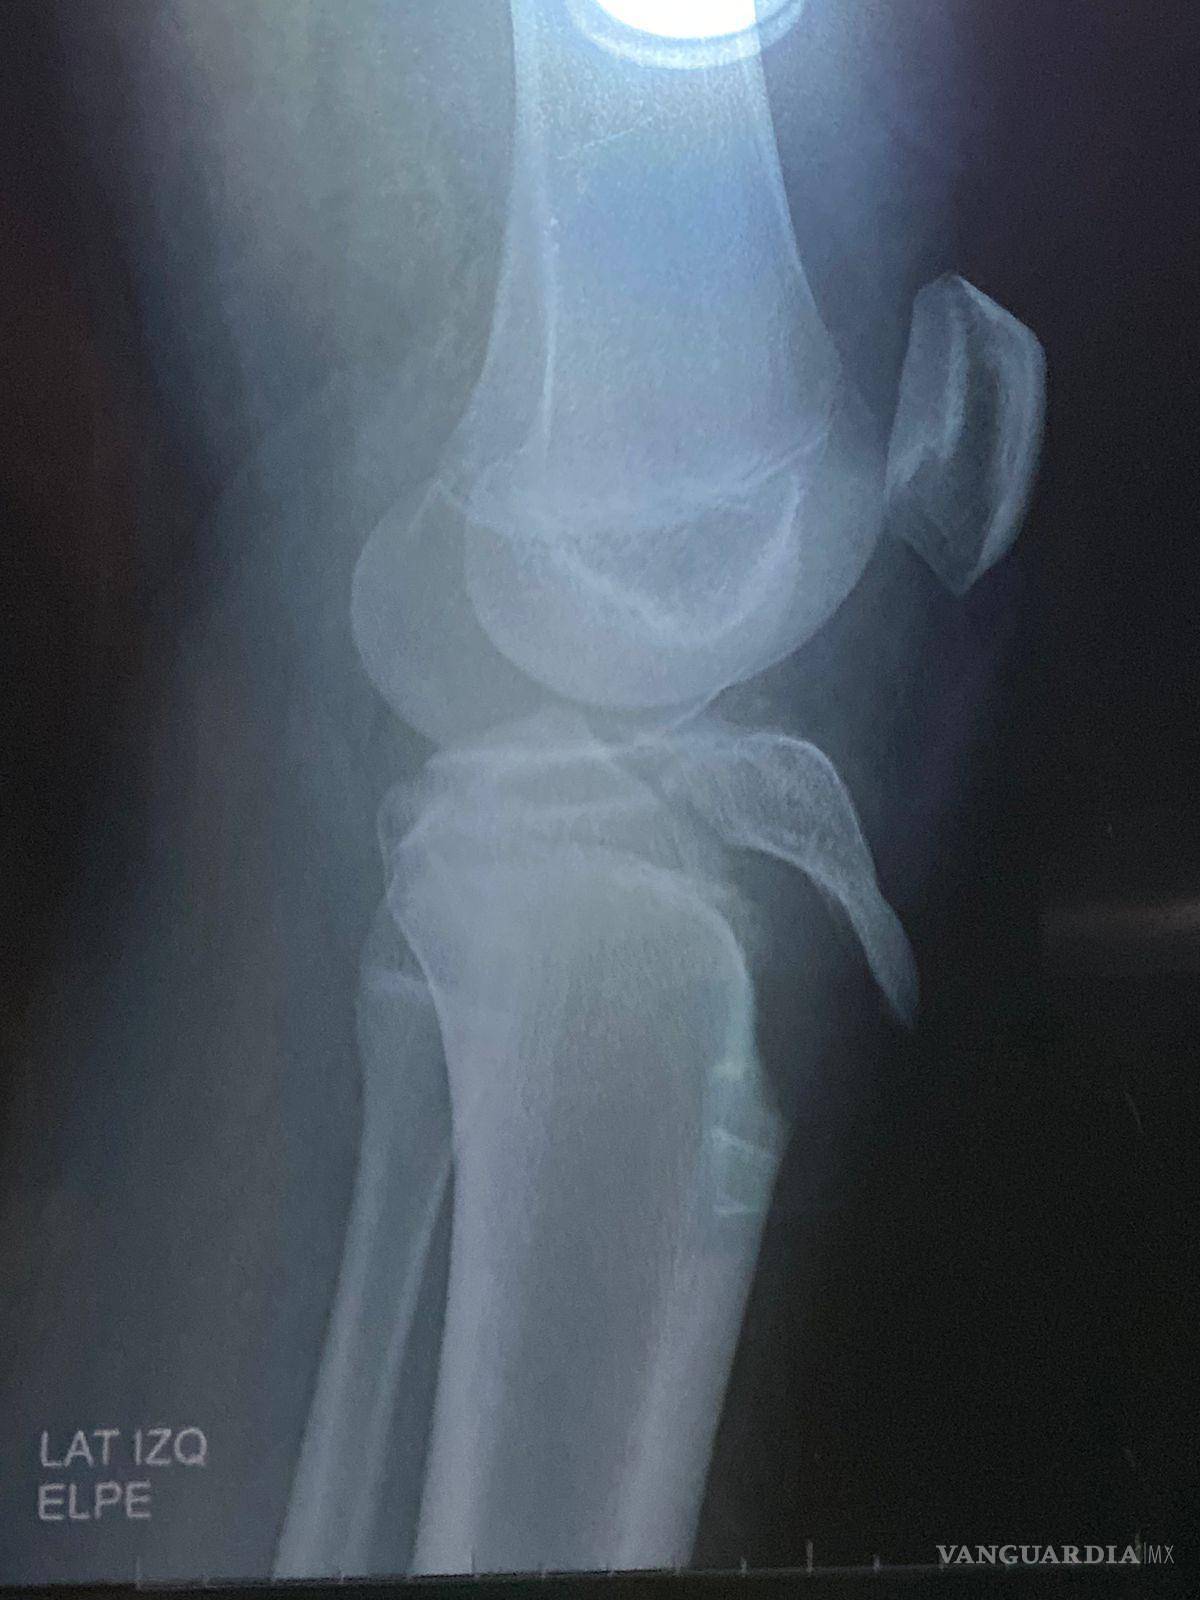

El menor participaba en prácticas para una actividad llamada “olimpiada” cuando resultó con una grave lesión en la rodilla que requirió cirugía para la colocación de tornillos.

$!La cirugía del estudiante implicó la colocación de tornillos en la tibia, costos que inicialmente cubrieron los tutores.

De acuerdo con la madre del alumno, la institución no llamó a una ambulancia ni siguió los protocolos establecidos para atención médica de emergencias. El estudiante fue entregado a su padre con la pierna manipulada y sentado en la recepción del colegio, sin que se contara con asistencia profesional inmediata, lo que pudo haber agravado la lesión.